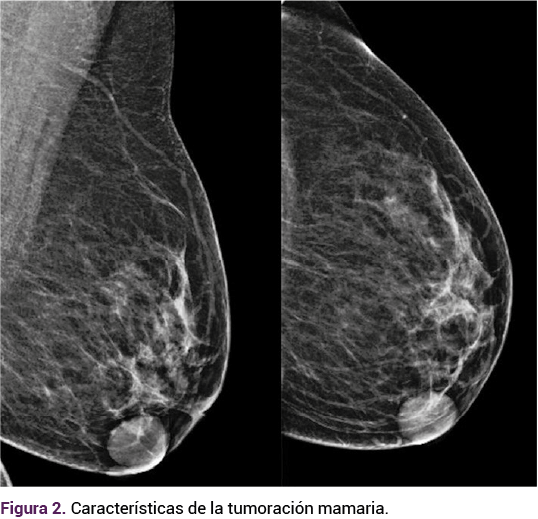

La ecografía (Figura 2) y mastografía (Figura 3) institucional reportaron: mama izquierda BIRADS 4A, nódulos sólido-quísticos (que requieren toma de biopsia), calcificaciones típicamente benignas, ganglios inflamatorios y la mama derecha con BIRADS 2.

<strong>Figura 2</strong>

Figura 2.